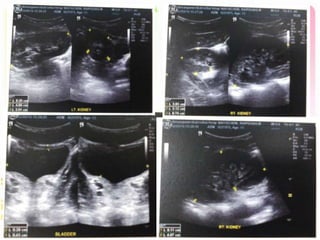

Film KUB

U/S KUB